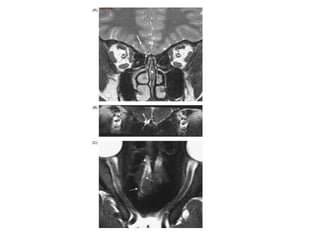

CAS N°1:

Femme 75 ans consulte aux urgences pour épistaxis droite.

Début remonte à 6 semaines: saignement modéré mais répété, rhinorrhée et

céphalées.

Elle prend des anticoagulants en raison d’une cardiopathie.

Examen endoscopique: muqueuse aspect normal, tache vasculaire normale.

Masse lisse comblant complètement la fosse nasale droite et le nasopharynx

avec quelques fines veinules en surface.la palpation du cou ne retrouve pas

d’adénopathies cervicales.

Adénome à prolactine de la glande hypophysaire.

L’épistaxis est rarement révélatrice d’un adénome hypophysaire.

Il s’agit surtout de manifestations d’une hyperprolactinémie: galactorrhée et

hypogonadisme.

Selon l’extension de la tumeur on obtient une symptomatologie supra sellaire:

céphalées et troubles visuels par compression du chiasma optique.

TRAITEMENT:

-bromocryptine

-chirurgie selle turcique par voie endoscopique